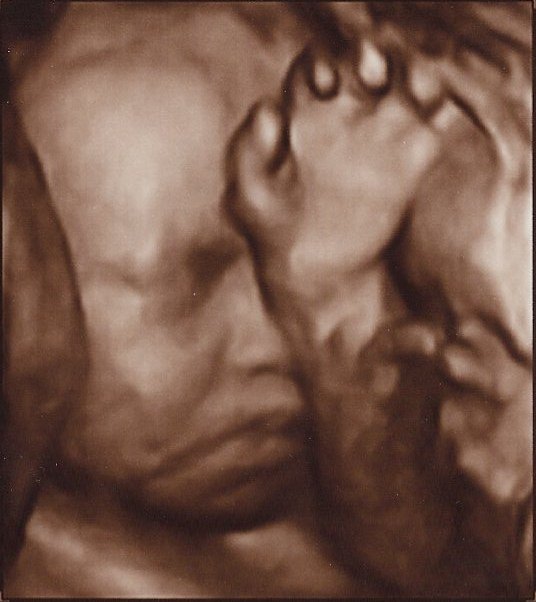

Det er så vildt at være til 3D scanning, det er som om, man er gravid på en helt anden måde bagefter

Ja, virkelig! Det er en hel anden måde at forholde sig til den lille på! Men når man ser billederne synes jeg man tænker "iih hun er stor", men hun er jo i virkeligheden stadig lillebitte. Lidt skægt